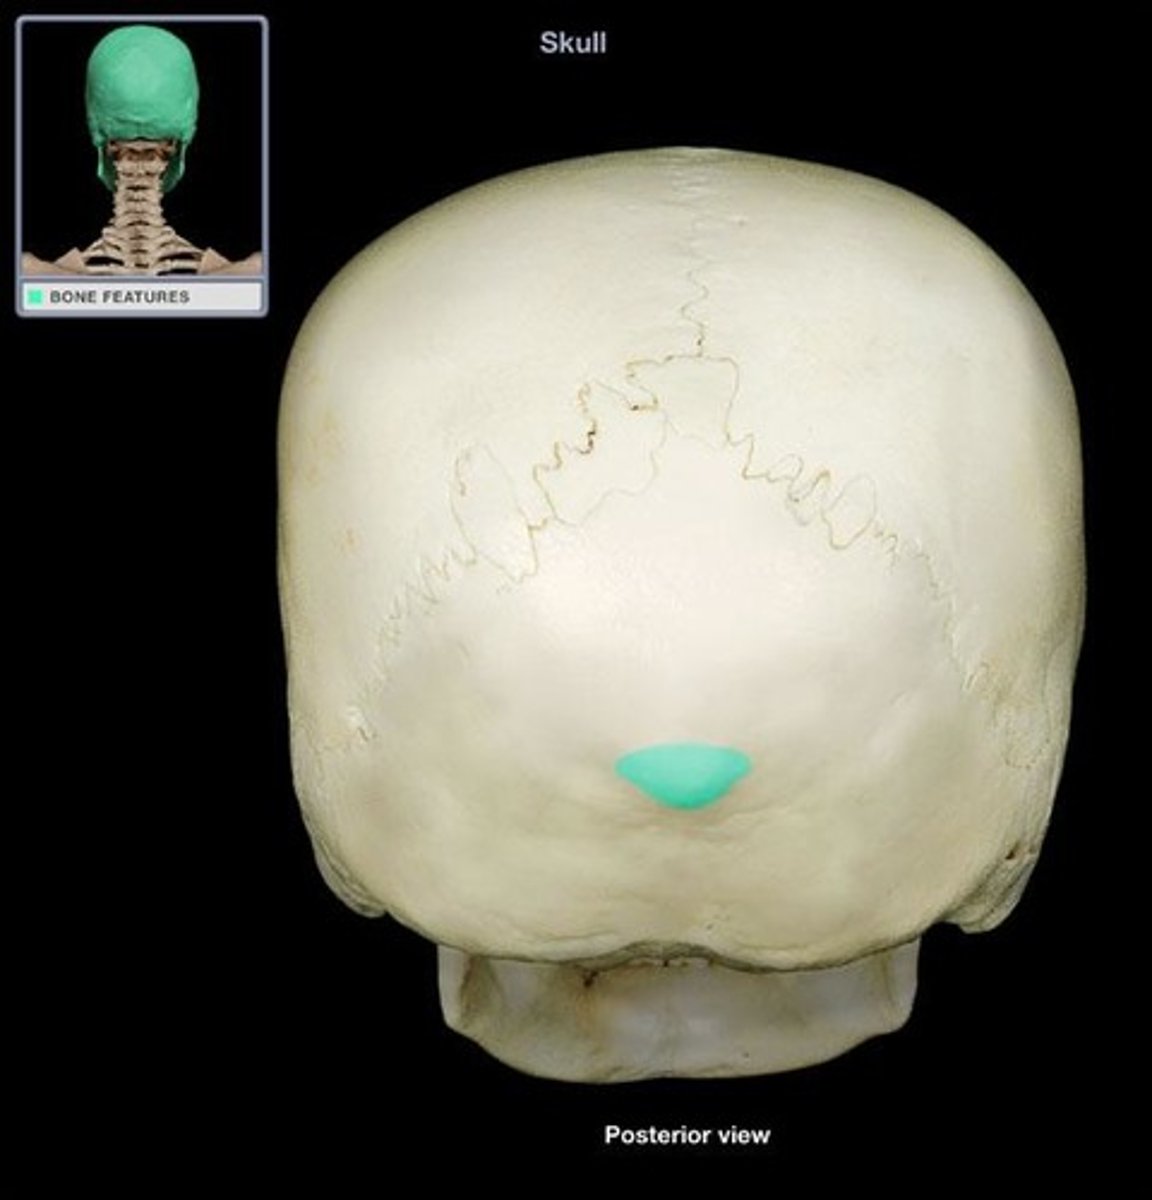

occipital bone

external occipital protuberance